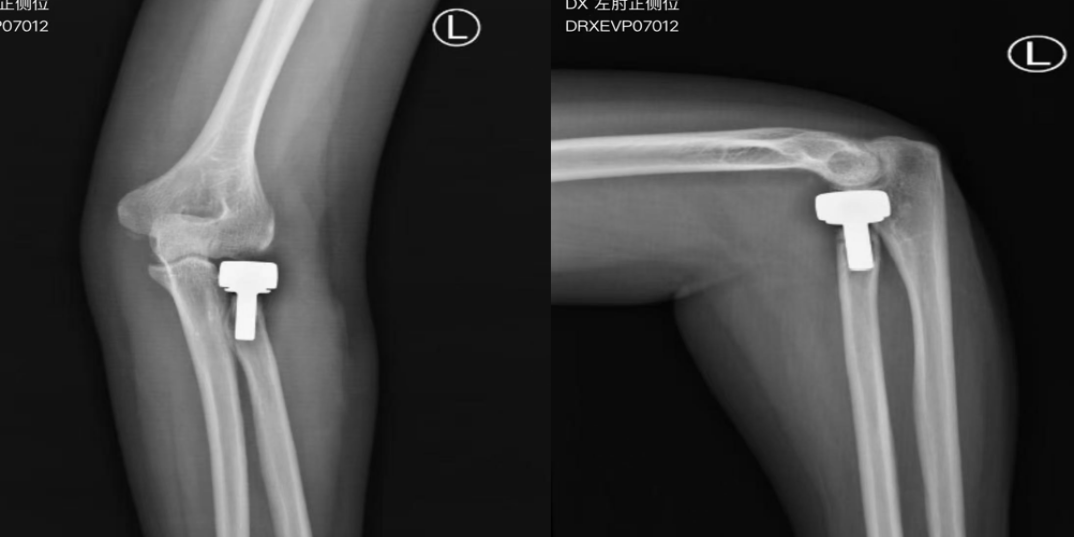

在异地就诊,张先生被确诊“桡骨小头粉碎性骨折”,随后紧急实施手术。术后1个半月复查时,张先生出现严重肘关节伸屈和旋转功能障碍,X线发现钢板固定的骨折发生明显的移位。

伤后X线发现桡骨小头粉碎性骨折及术后1.5月发现钢板固定后的桡骨小头再次错位